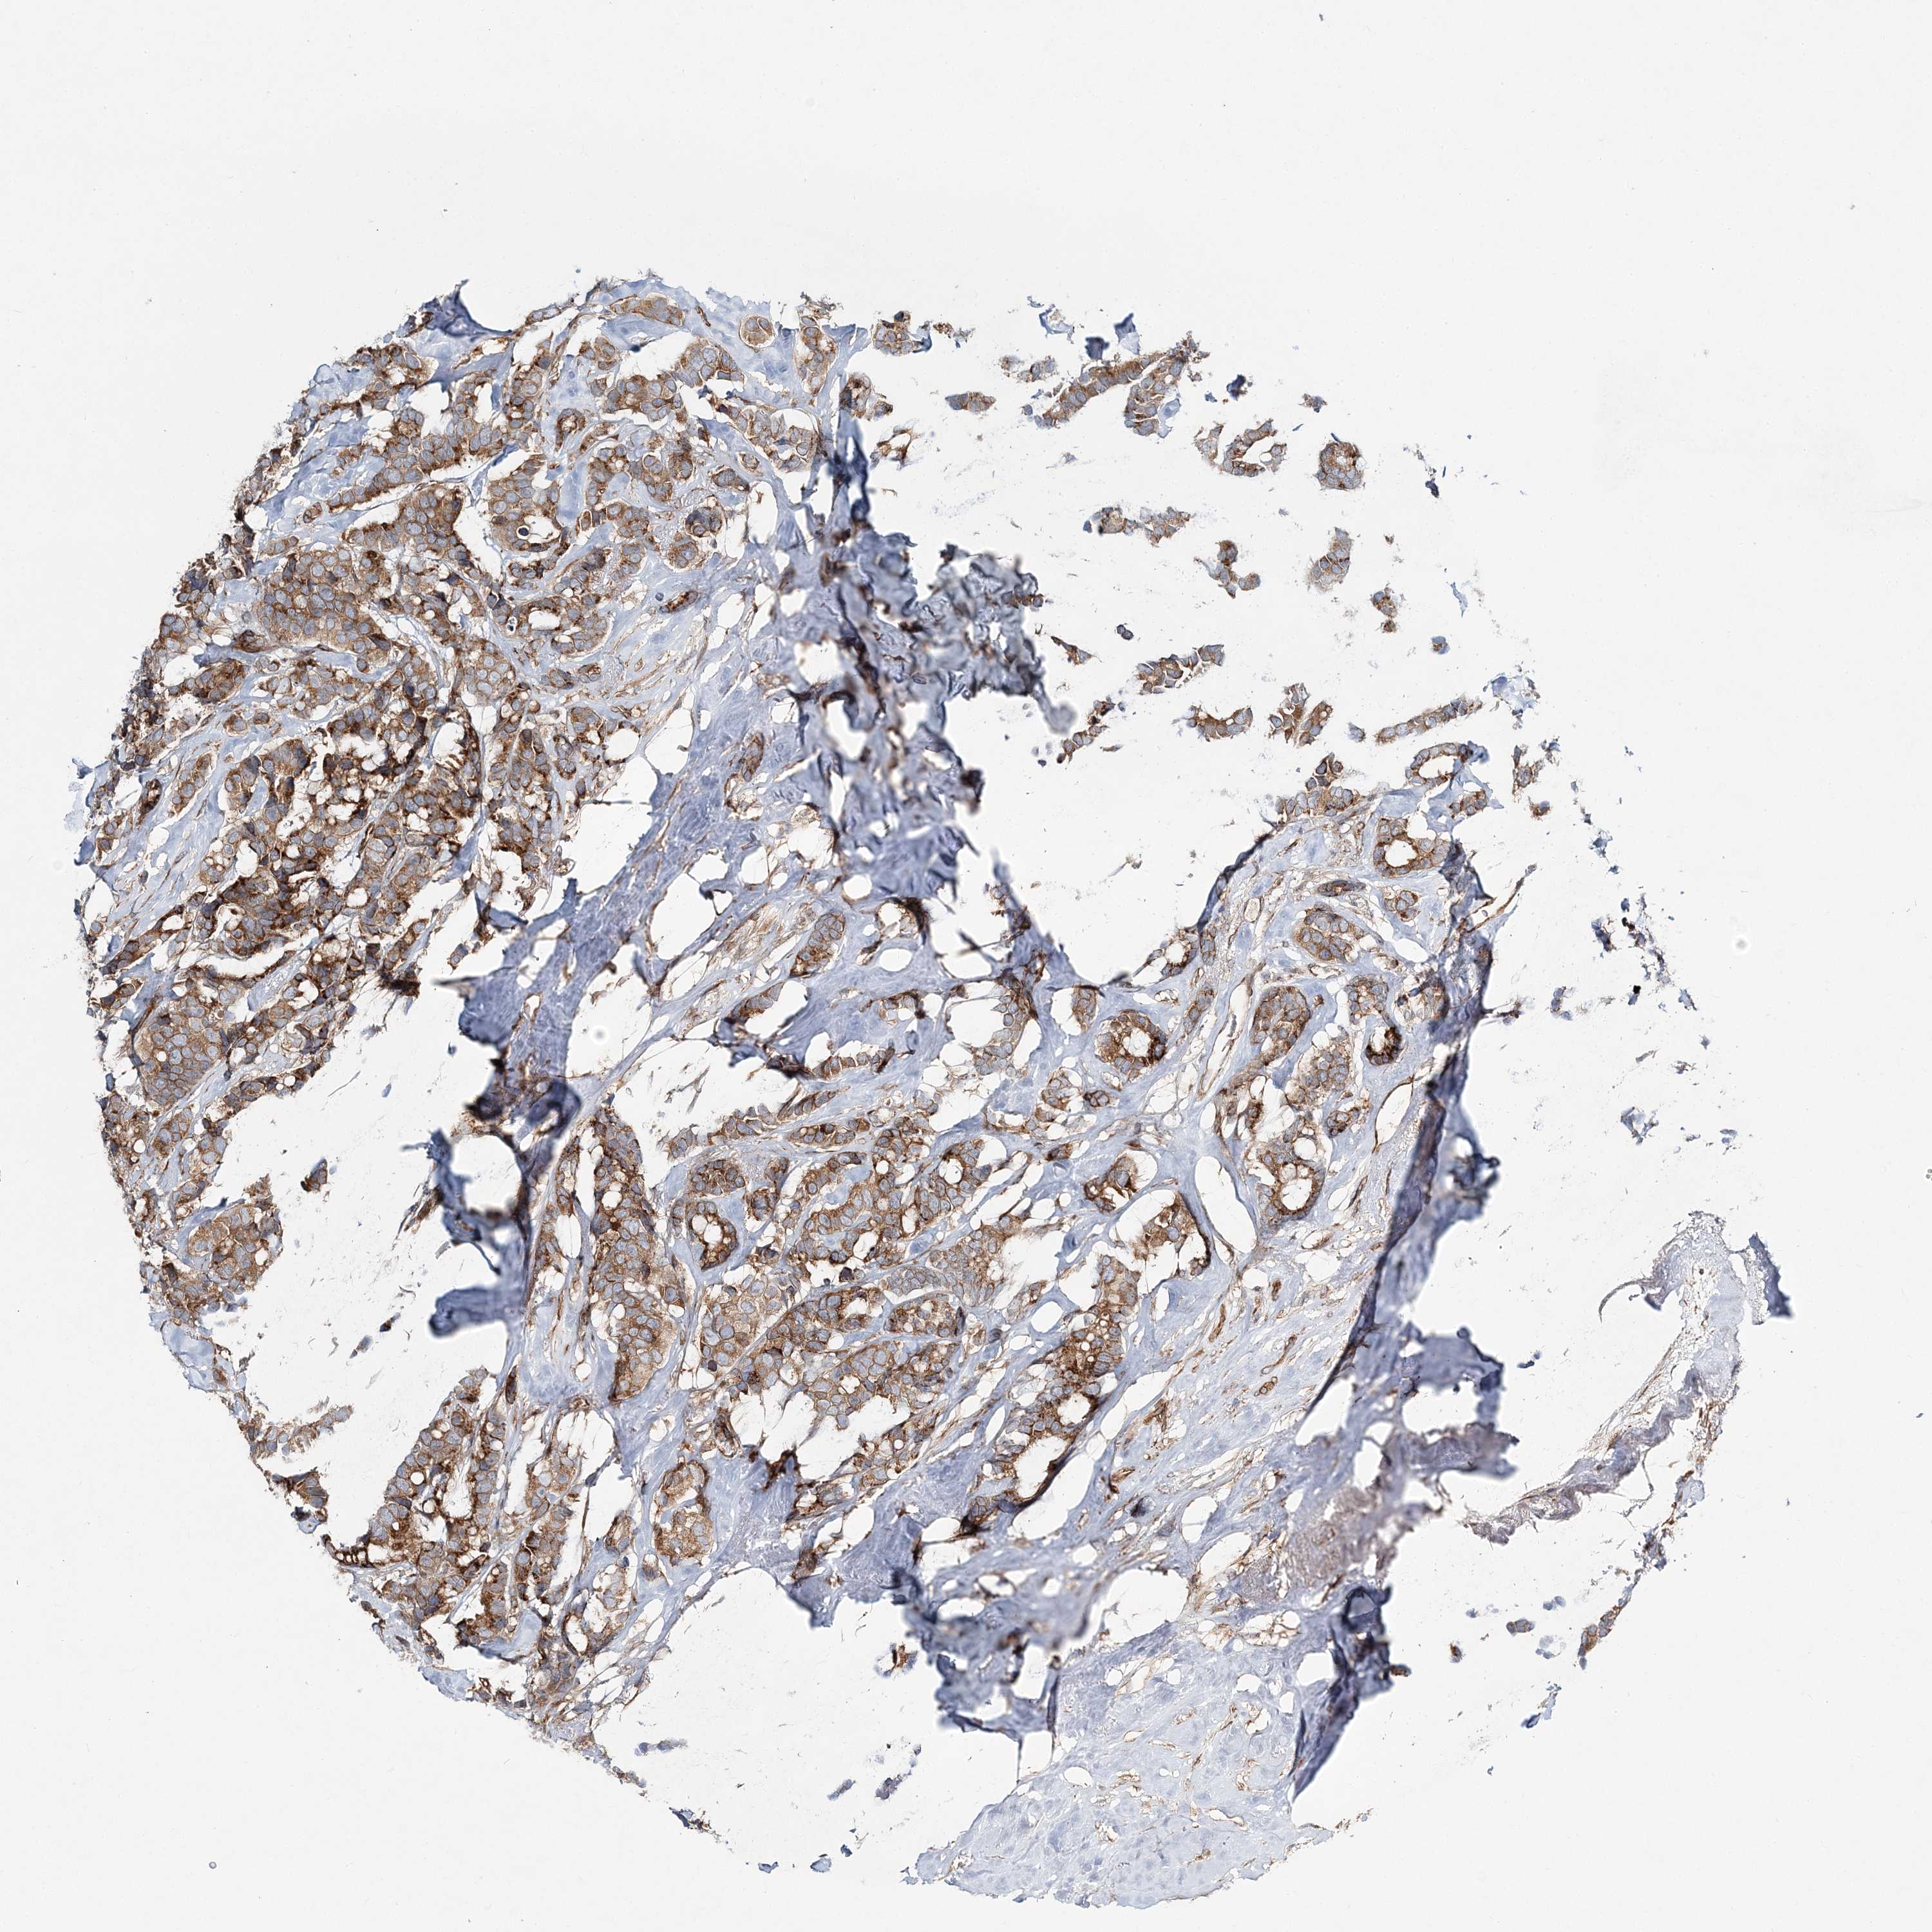

CANCER BREAST CANCER Show tissue menu

BRCA TCGA BRCA VALIDATION PROTEIN EXPRESSION